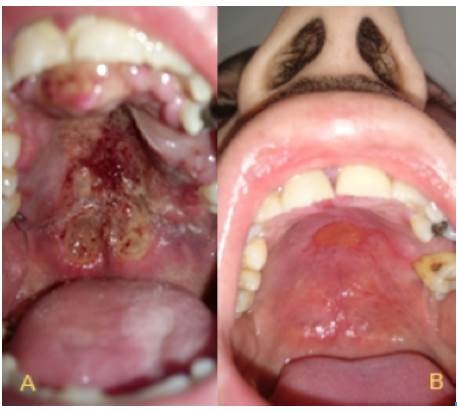

This case presents a 31-year old mestizo male patient, born in Fusagasugá, Colombia, with a history of inhaled cocaine and tobacco abuse. He works as a painter, with constant exposure to inhaled chemicals. The month prior to consultation, he was treated for acute sinusitis with amoxicillin for 10 days due to bilateral nasal obstruction and occasional epistaxis. Three weeks before consultation, he noted a painful ulcer in the hard palate, although, no systemic symptoms were reported. On general examination he was cachectic but stable, and presented with hyponasal speech. Rhinoscopy showed a bilateral mass in the nasal cavity with septal perforation in Cottle zones 2 - 3. Hard and soft palate showed a necrotic lesion with irregular borders, mucosa swelling without active bleeding. He had no palpable adenopathy on head and neck (Figure 1).

Ulcerated lesion in hard palate with necrotic borders. Circle: Delimitation of the site of the biopsy.

Figure 1: Ulcerated lesion in hard palate with necrotic borders. Circle: Delimitation of the site of the biopsy.

The final staging was T4, N1, M0, ECOG 1, IPI of low/intermediate-risk in a patient with poor health condition. The patient underwent chemotherapy with SMILE protocol (Table 1). Only 2 courses of SMILE were administered with adequate tolerance and some side effects, which were easily managed, such as queasiness, vomiting, weight loss and alopecia. Figure 4 shows the improvement of the lesion seven months after initiation of treatment; finally, after ten months of clinical and radiological surveillance, there was a complete remission of the lesions in oral and nasal cavity. In addition, the patient reported improvement of nasal obstruction and pain in the palate by 90%, but left amaurosis was persistent.

A. Initial lesion in the palate. B. 7 months after SMILE protocol chemotherapy.

Figure 4: A. Initial lesion in the palate. B. 7 months after SMILE protocol chemotherapy.